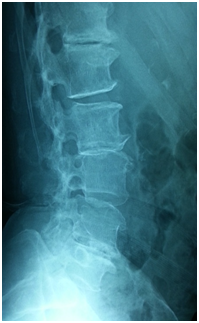

- Anterior column reconstruction with cages especially at Lumbo- sacral junction is necessary and always required to restore sagittal balance (Figure 3).

Figure 3 Flat back syndrome.